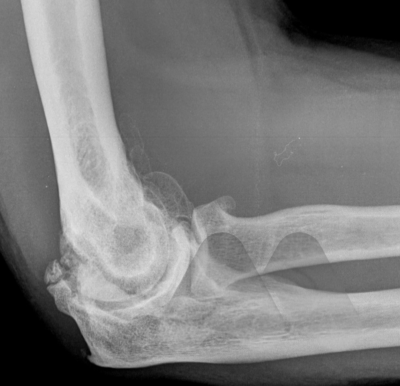

Elbow osteoarthritis is a degenerative joint disease where the smooth cartilage covering the bone ends, wear out, causing pain and stiffness. It can affect younger patients where a previous traumatic injury can lead to either ligamentous instability, severe scarring in the joint or cartilage injury and lead to progressive stiffness around the elbow which may or may not be accompanied by pain.

In cases where the main complaint is stiffness in the elbow, common activities like shaving, getting to the back of the head and face become difficult. X-Rays are a simple scan that can confirm extra bone formation in the joint which may be blocking movement. In these situations, a keyhole operation (arthroscopy) can be performed to remove loose fragments of bone, remove extra bone and release the tight capsule that surrounds the joint.

Pain in the elbow can relate to the inflammation of the joint lining (synovitis) that accompanies osteoarthritis or impingement related pain at the end ranges of movement where bone fragments can jam between the joint surfaces. If loose bodies are present in the joint, these can float around freely and intermittently cause jamming of the moving parts like a loose stone in a motor. Depending on the cause of pain, the treatment can be directed at reducing the inflammation with oral anti-inflammatories or corticosteroid injections to the joint. Surgical treatments include arthroscopic or open debridement of the joint to remove extra or loose fragments of bone that are impinging. If there is extensive joint involvement and these simple measures fail to relieve pain then a Total Elbow Replacement can provide good pain relief whilst maintaining movement.